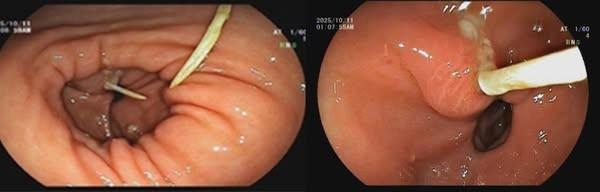

Kết quả nội soi dạ dày cho thấy: Sát môn vị có hình ảnh mảnh xương dài khoảng 3cm cắm vào thành dạ dày, vùng xung quanh phù nề, xung huyết nhiều và có loét. Khai thác tiền sử bệnh nhân cho biết, cách ngày vào viện 4 ngày bệnh nhân có ăn cháo gà, sau đó chỉ đau bụng âm ỉ nên chủ quan không đi khám.

Với sự phối hợp của các chuyên khoa, Bệnh nhân được tiến hành gây mê, nội soi can thiệp gắp dị vật, làm sạch vùng tổn thương và xử trí ổ loét.

manh-xuong-ga.jpg

Mảnh xương đâm xuyên dạ dày tạo ổ áp xe